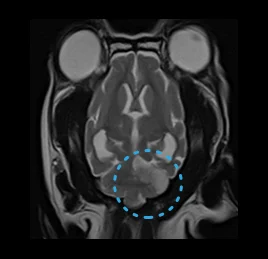

• 허혈성 소뇌경색